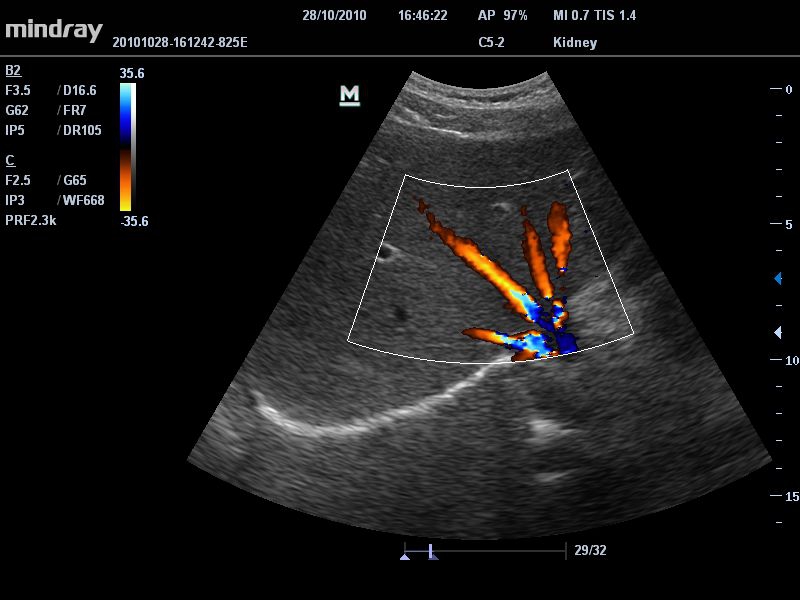

Общая визуализация:

Да

Ветеринария:

• Режимы сканирования: B/M/CFM/PDI/Направленный PDI/PW, HPRF, Тканевая гармоника, М- и цветной М-режим.